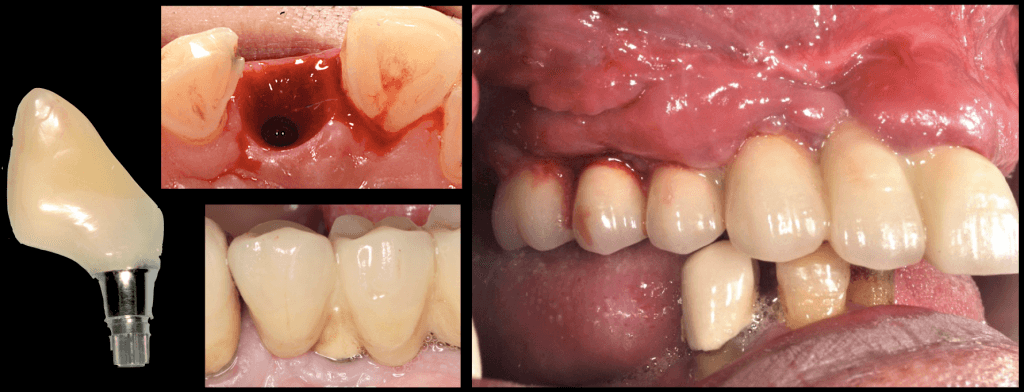

Nr. 1: Keep the roof clean!

Imagine a house with a large roof, with no access for the cleaners, blocked drainage, where the rainwater piles and the pigeons nest. Soon the piles of bird pooh will emerge through the pools of rainwater, Mosquitos will join the party and birds will thrive, but the human tenants will be driven away.

In the supracrestal complex, the roof is the crucial couple of millimetres of the prosthesis slightly above and slightly below the margin of the soft tissues. This is the surface of the prosthesis which first meets the soft tissues and it is crucial because this is where the Biofilm forms. If this is uncleanable, inflammation of the supracrestal complex is only a matter of (short) time.

Nr. 2: Mind the Gap!

Every technical construction has gaps between its components. Implant, abutment, screws, prosthesis, they all come with certain gaps, sometimes acting protectively and sometimes to the detriment of the complex.

They can be “microgaps” of 1-2 μm or “megagaps” of 100 μm, they can be deep near the bone, or high up in the sulcus, sugingival or supragingival. Knowing which gaps to accept and which to avoid is essential, as this is a risk that can be minimised through the correct design of the prosthesis and selection of implant and prosthetic components!